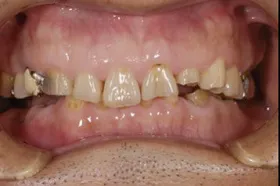

金属を白くし、歯茎の黒ズミを改善したケース

■治療前

■治療後

| 主訴 | 全体的に白い歯にして見た目をきれいにしたい 歯茎が黒くなっているのが気になる、歯ならびも良くしたい |

| 治療方法 | 矯正治療+歯茎の黒ずみの改善+補綴治療 |

| 治療期間 | 3年 |

| 通院回数等 | 約40回 |

| 費用 | 約350万円 |

| リスク・副作用 | 矯正治療も行ったので治療期間が長くなった |